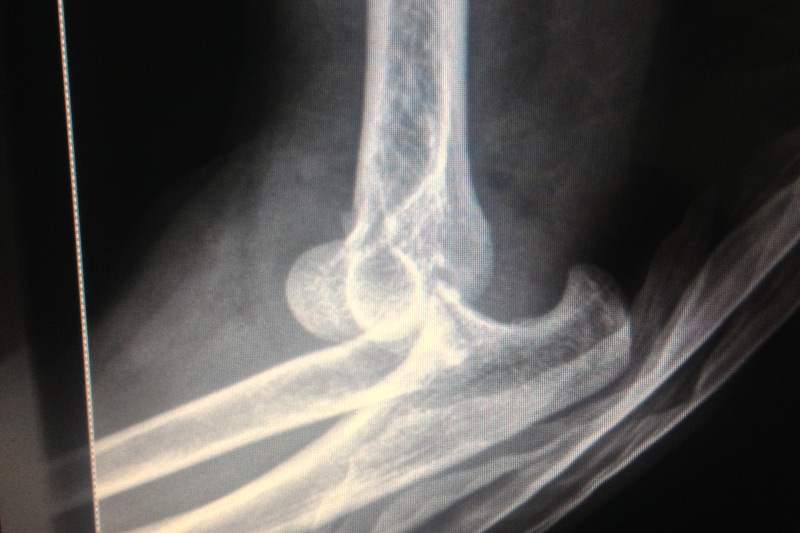

La práctica deportiva diaria de alto impacto, implica riesgo de lesiones incluyendo fracturas, ruptura completa de ligamentos cruzados, lesiones meniscales, incluso esguinces de diferentes grados, contamos con la capacidad científica y tecnológica para poder resolver estas patologías con el menor número de secuelas y con pronta reincorporación a actividad deportiva..

• Fracturas en el adulto y niños

• Fracturas complejas de alto impacto

• Ruptura del ligamento cruzado anterior y lesiones meniscales